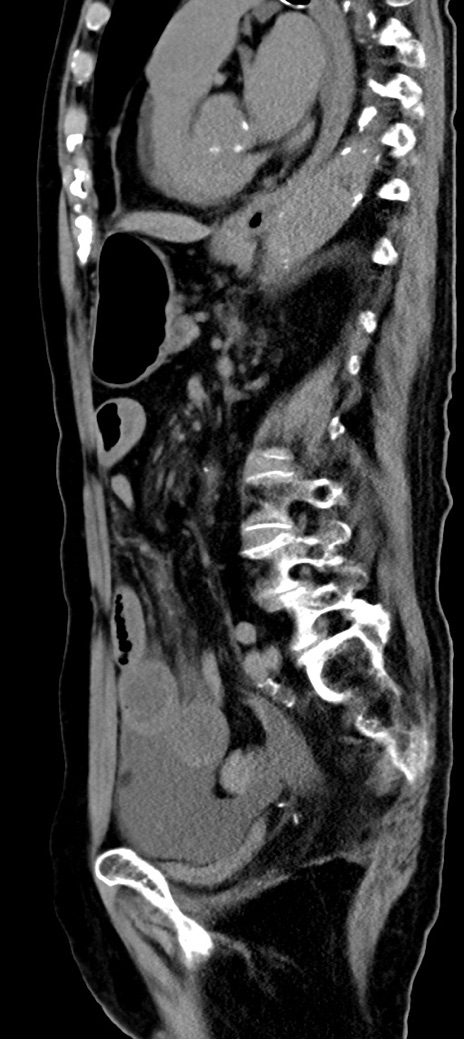

冠状断像